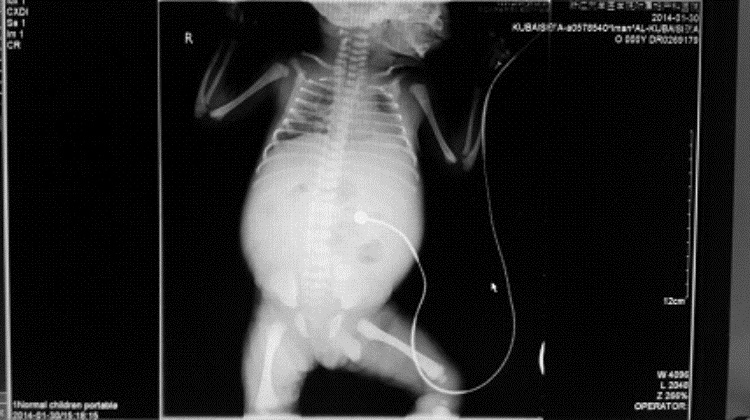

停经37+2周B超示:胎儿腹腔内12.2 cm×9.2 cm×7.2 cm液性暗区,内见分隔样回声,透声差(图 1),同日阴道分娩一男婴,Apgar评分8~9分/1~5 min,体质量2 750 g。新生儿查体:腹胀明显,腹部X线结果:腹部膨隆,两侧膈下无游离气体影,腹腔内中下腹部见不规则团片状及点状稍高密度及高密度影,最大为1.6 cm×1.2 cm,腹内显示少许肠管内有气体,未见明显气-液平面,诊断结果:腹腔囊肿,畸胎瘤?(图 2)。初步诊断:先天性腹腔囊肿,需手术治疗转入浙江大学医学院附属儿童医院。

| 图 2 新生儿腹部X线结果 |